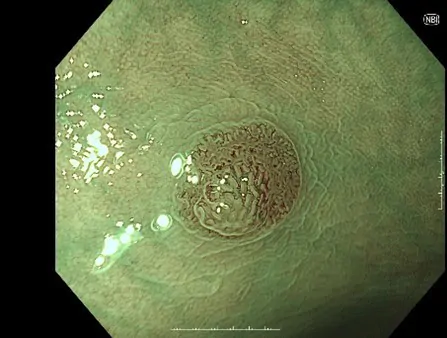

大腸カメラの症例

TXI(Texture and Color Enhancement Imaging)

色調の変化が小さい病変や凹凸の少ない平坦な病変は見つけにくいことがあります。この課題をクリアするために登場した「TXI(Texture and Color Enhancement Imaging)」は、画像処理技術によって病変をより見つけやすくすることを目指した画像強調技術です。

TXIは、粘膜表面の「構造」「色調」「明るさ」の 3 つの要素を最適化する画像強調技術です。通常光観察では見づらい画像上のわずかな色調や構造の変化が、TXI を活用することにより強調され、病変部などの観察性能向上に貢献することが期待されます。